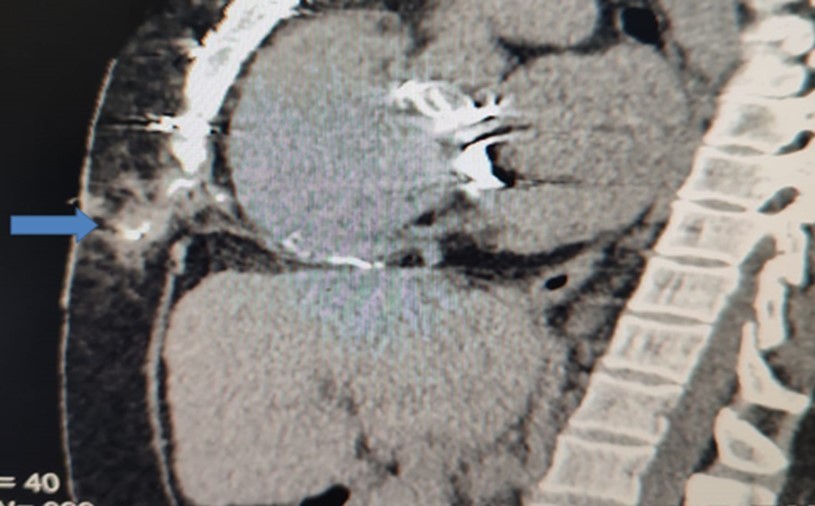

After weaning from cardiopulmonary bypass, as per institutional protocol for heart-valve operations, right atrial and /or right ventricular epicardial and diaphragmatic pacing wires (Quad Polar, 250 cm, Medical Concepts Europe (MCE), MCE Gemert, Netherlands) were inserted. Atrial wires were fixed with 5/0 prolene sutures taking superficial bites on the surface of the epicardial surface layer just to ensure gentle contact with the heart muscles and minimize complication rate 3, 5. The exit site in the epigastrium to the right of the midline was secured with a 2/0 silk suture. After an uneventful recovery in intensive care, each patient was transferred to the ward. As per institutional protocol, all postoperative cardiac surgical patients receive low molecular weight heparin subcutaneously as a prophylaxis against deep vein thrombosis The DVT-prophylaxis is continued until the day of discharge or when the patient is fully ambulatory. We do not stop the prophylaxis before temporary Pacemaker Wire-removal. On the 4th postoperative day, the pacing wires were pulled out with gentle traction. In centers other than ours, some surgeons only excise the external portion of the wires. This was complicated with chronic abscess and sinus formation years after surgery (Table 1). Diagnosis was confirmed radio-logically (Figure 1).

Figure 1.Sagittal CT-section of chest showing the extension of the sinus track containing the contrast

b) Computerized tomography with mild push of contrast to the sinus track (Figure 1)